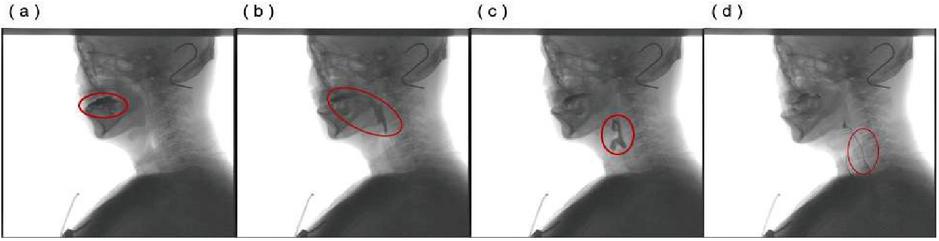

images

Figure 2 This case demonstrates a simplified procedure for the extraction of a patient’s piriform fossa.

The premise of our work is to judge a single frame from the original barium recognition, and gradually transfer to the determination of tissues and organs through the barium recognition. Why accurate tracking, only the complete track of barium agent, to facilitate the later determination of barium agent in each organ stay position, time and quantitative study. We used morphological methods to extract barium. Due to the quality difference of the original film, the expected errors of the barium trace area deviation in this experiment were within -25%25%.